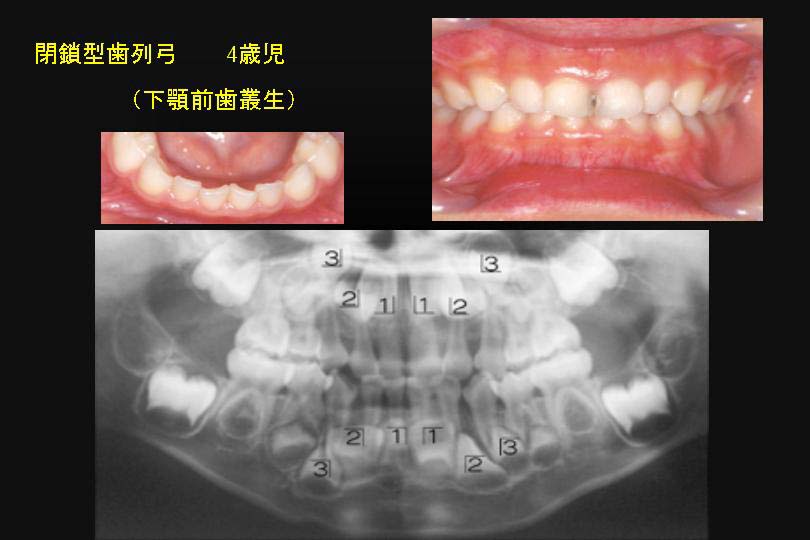

一方、閉鎖型歯列弓では、下顎の永久側切歯は中切歯より大きく写っている。

これは下顎の中切歯より、側切歯が舌側にあることを意味している。(図6)

図6

図6:乳歯の閉鎖型歯列弓は、下顎永久側切歯は、舌側へ萌出する可能性が高い。